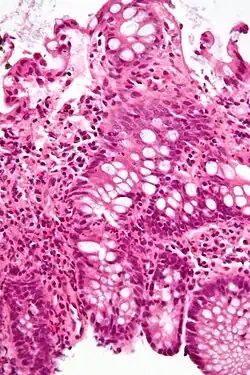

O diagnóstico se dá geralmente através de colonoscopia com biópsia das lesões patológicas.